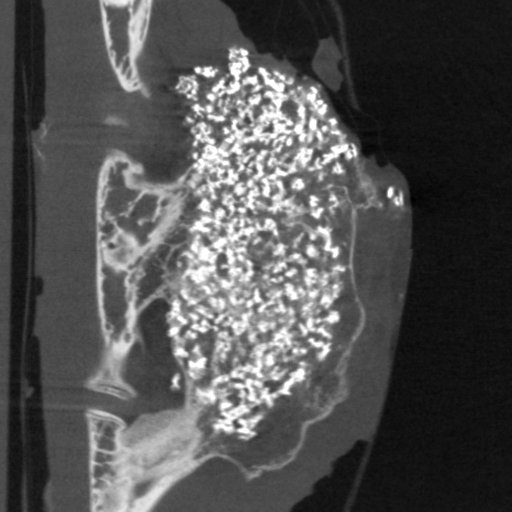

For her research, Nada used synthetic implants made from calcium phosphate, a common material in bone repair. “On their own, these implants are quite passive in the body,” she explains. Nada and her team asked: could we make the implants encourage healing by gently stimulating the immune system? To test this, they added small, inactivated fragments of bacteria and fungi. “It’s a bit like vaccines”, Nada says. “You only need small parts of the microbe to trigger a useful response.”

Certain immune stimulants stood out. “Peptidoglycan (part of bacteria) and BCG (vaccine) gave us signals that bone formation was happening”, Nada says. Although most of the tested substances had little effect, these findings showed that the immune system is not a passive player in bone healing.